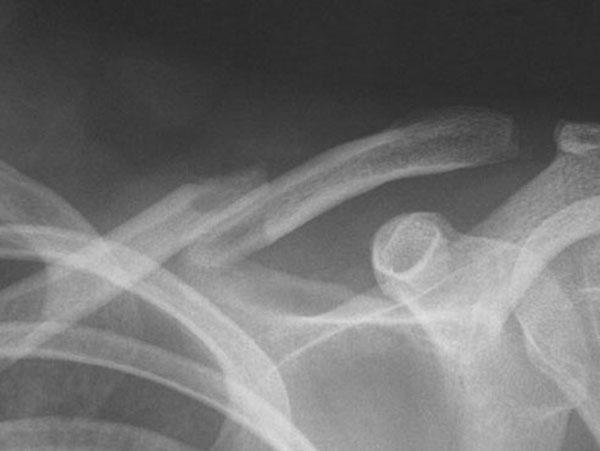

What do Distal Clavicle Fractures Look Like on X-ray and CT?

X-RAY

Click an image to enlarge

Diagnosis of a distal clavicle fracture is made with history, then a plain xray of the clavicle and in a lot of cases a CT scan. With new 3D CT scan imaging, separation of bony fragments can be well visualised which helps for possible surgical planning.